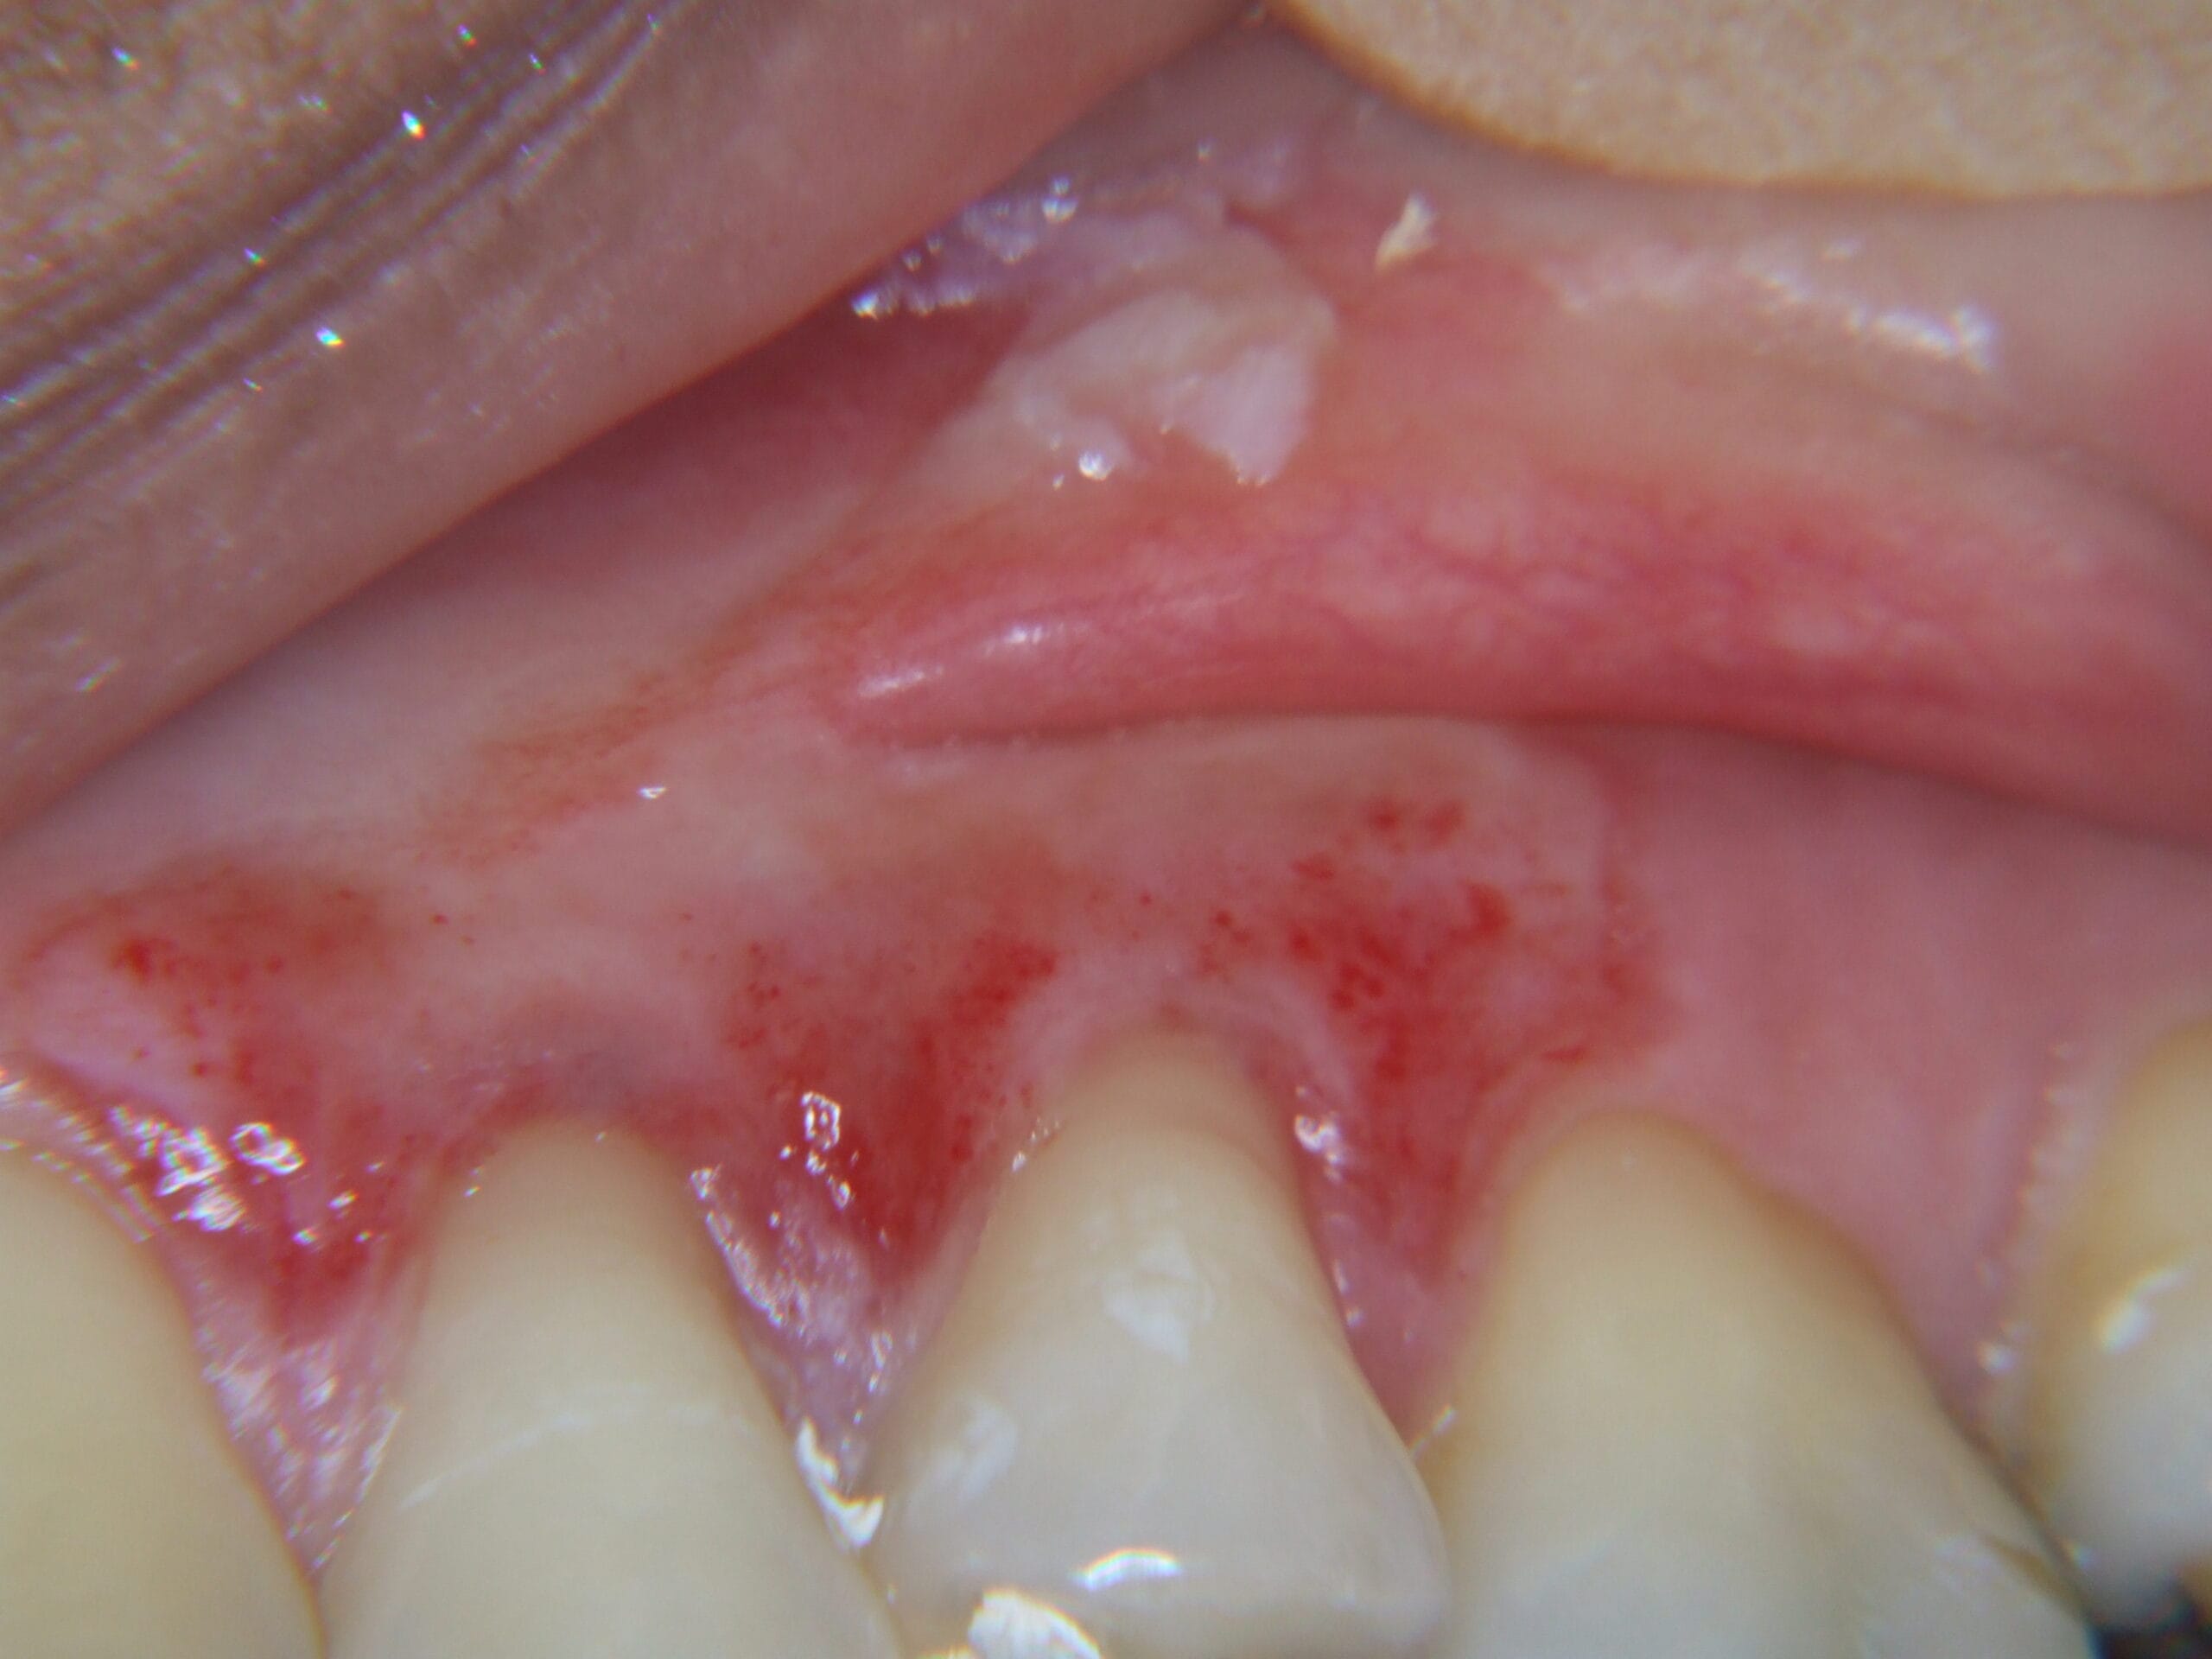

Muitas pessoas pesquisam “remédio caseiro para dor de dente” ou “como aliviar dor de dente rápido”. A própria ADA (Associação Dentária Americana) alerta: colocar aspirina ou qualquer substância diretamente no dente causa queimadura química. Veja casos reais de pacientes que se automedicaram:

Paciente aplicou Anestesiol e dormiu com o produto na boca. Acordou com necrose severa.